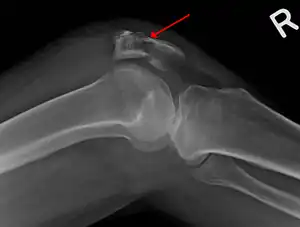

Osteochondral fracture of patella

Some people have a normal two-part patella which can appear as a fracture. The fragment is usually seen in the top outer corner of the patella and can be distinguished from a fracture by being present in both knees.[6]